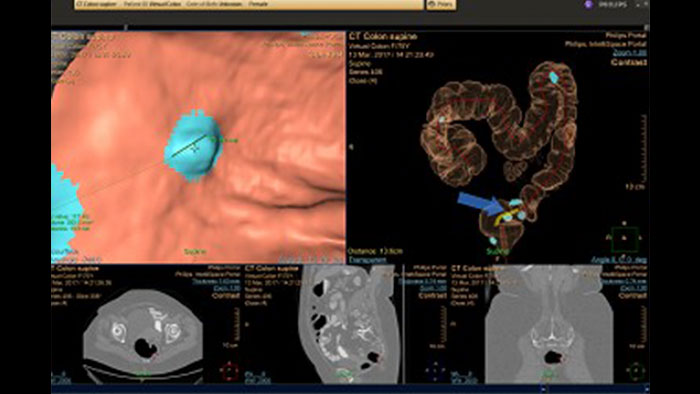

Virtual Colonoscopy

CT Virtual Colonoscopy

Reducing reading times in virtual colonoscopy

Enables 3D visualization of colon scans. The application automatically segments the air-filled colon and displays a calculated navigation path. The Perspective Filet view provides a synchronized display of the full colon surface wall with a single unidirectional view, reducing the need to review in both directions.

Benefits

• The Electronic Cleansing function can reduce the effect of residual liquids and fecal materials by "tagging" them via contrast-enhancement, allowing the user to automatically segment and subtract them.

• The CAD option* can be used as a second reader and assist in the search for polyps.